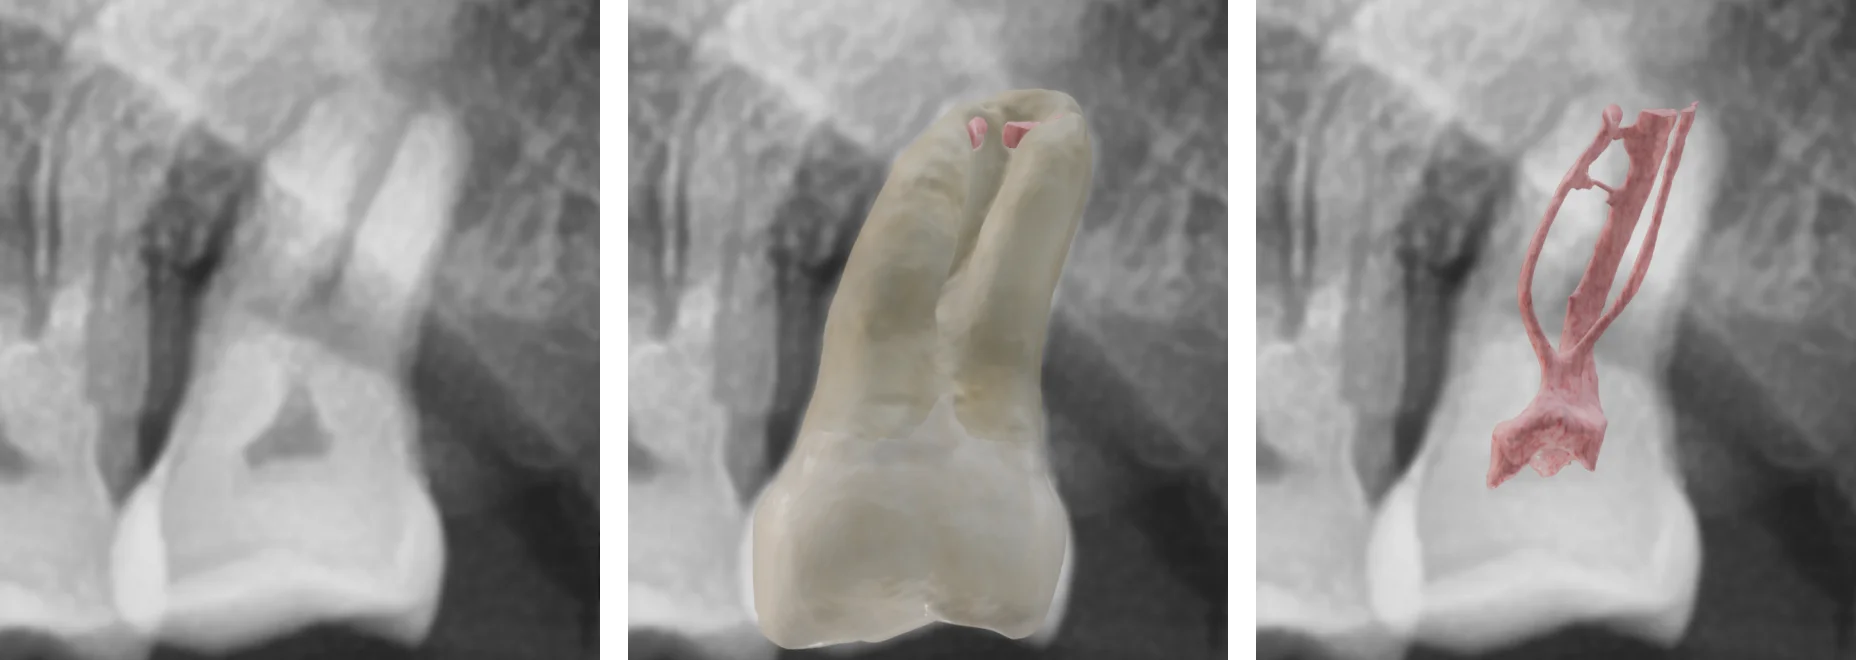

Instead of guessing, we’re jumping straight to the ground truth by superimposing a real 3D model of the extracted tooth onto the radiograph.

Radiographic images and 3D models of tooth root canals

Using Dental EndoMaster’s advanced 3D tooth models, we can align the extracted tooth model onto the radiograph using clear anatomical landmarks.

An image of a 3D model superimposed on a radiographic image.

Look at that! Now we can visually trace the roots with confidence. Instead of working in 2D, we're reconstructing the true 3D anatomy in our minds.